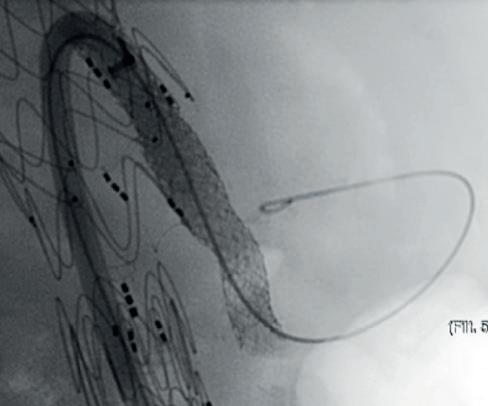

At ESVS 2022, Joost van Herwaarden (Utrecht University Medical Center, Utrecht, The Netherlands), who disclosed a research collaboration with Philips, spoke on the benefits and drawbacks of some of these technologies, speaking first on robotic navigation. He highlighted its ability to reduce radiation exposure for the operator and increase accuracy of catheter positioning, while acknowledging that the technology still carries the limitations associated with fluoroscopy use, due to its requirement for navigation.

According to Van Herwaarden, electromagnetic tracking addresses the limiting factors of greyscale images, offering instead brightly coloured images, as well as 3D navigation of devices, unlimited viewing angles, and no radiation, with the limited numbers of wires and catheters being a drawback.

Fiber Optic RealShape (FORS) technology from Philips also shows potential in this space, offering the benefits of 3D navigation, unlimited viewing angles, and the radiation-reducing benefits associated with the use of light instead of fluoroscopy, Van Herwaarden highlighted. He noted that one drawback is the fact there are only a limited number of devices available.

Finally, the presenter gave an overview of the pros and cons of image fusion. He stated that there is one system in this space—the Cydar Medical system—that offers automated registration. This technology compares the anatomy visible on live fluoroscopy with anatomy of a preoperative computed tomography angiography

(CTA) and automatically produces 3D overlay, he explained. According to the presenter, this technology offers “a significant reduction of contrast agent and also reduction of procedure time,” despite having a somewhat “complex setup”. Image fusion is “widely available” and, in the presenter’s opinion, “should be used in all complex procedures”.

Van Herwaarden summarised that these technologies show radiation-reducing potential, the small number of available publications suggest that these techniques are “still minimally applied”. According to the presenter, the future of these technologies lies in their combined use. For example, he said that, while electromagnetic tracking and FORS are “still under development,” they do offer “an even greater promise for simplifying complex procedures and realising dose reduction for patients and for staff,” when used in combination with IVUS or a robotic navigation system.